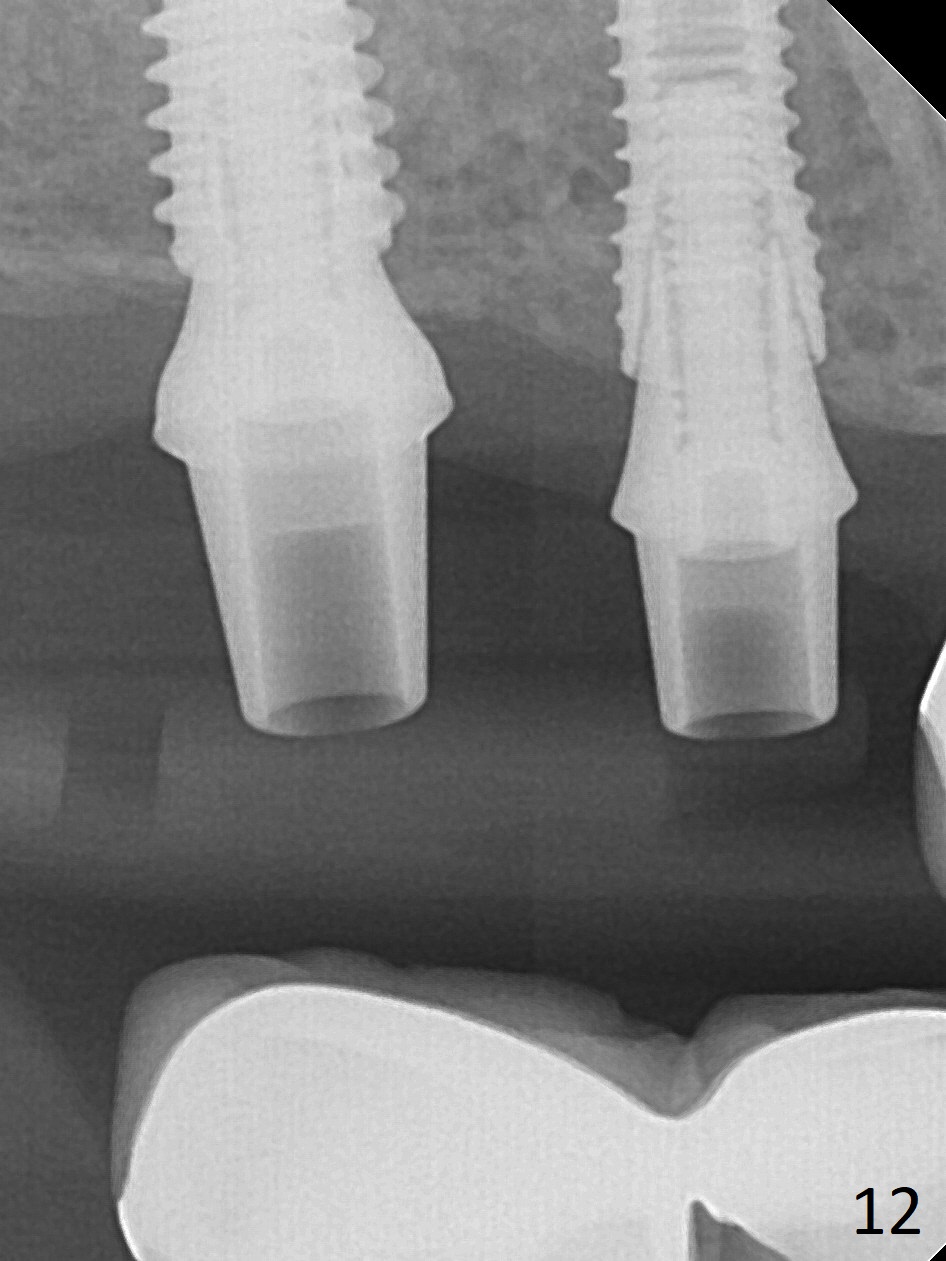

The ridge at #3,4 is wide (Fig.1). A surgical stent is placed (Fig.2) for initial osteotomy (Fig.3). When the stent is removed, the osteotomies need to move palatal (Fig.4 arrows). As two of 1.2 mm drills are in place (Fig.5), mesiodistal trajectories are found off (Fig.6). After the trajectories are corrected (Fig.7), the depth cannot be determined with PA (Fig.8, as compared to Pan (Fig.9)). Following 4.3 and 3.2 mm final drills at #3 and 4, 4.5x13 and 3.8x15 mm implants are placed with insertion torque of 35 and 50 Ncm, followed by 5.5x4(3) and 4.5x4(2) mm abutments (Fig.10). BWs show incomplete placement of the implant at #4 distal (Fig.11,12). Later the implant is placed ~ .5 mm deeper. Periodontal dressing is applied postop. CT-assisted surgical guide must be more efficient for this case with wide ridge. There is no bone loss around the implants 3 moths postop